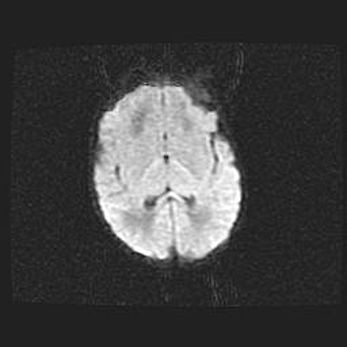

Церебральная ишемия II.

Возраст: 7 дней

Вес: 3350 г

Пол: женский

Окружность головы: 35 см

Срок гестации: 39 недель

Ишемия головного мозга – это состояние, которое развивается в ответ на кислородное голодание вследствие недостаточного мозгового кровообращения. У новорожденных она является следствием дефицита кислорода, что ведет к метаболическим расстройствам различной степени тяжести в тканях головного мозга, в том числе к развитию коагуляционных некрозов и гибели нейронов.